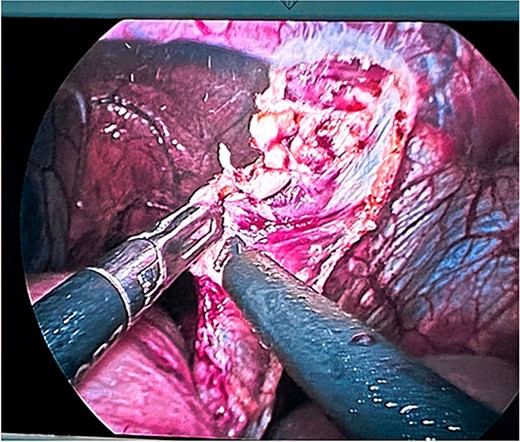

Surgical treatment was decided. Five ports were used: one supraumbilical 12 mm port for the telescope, one 5 mm subxiphoid port for the liver retractor, and three working ports placed in the left midclavicular line of 12 mm, the left axillary line of 5 mm, and the right midclavicular line of 5 mm. A type IV hiatal hernia was found with a 12 cm hernia defect (Fig. 3), a hernia sac measuring 20 cm × 15 cm × 7 cm, containing the entire stomach, dudodenum, pancreas, greater omentum, and transverse colon. The content was reduced to subsequently dissect and resect the hernia sac (Fig. 4).

Dissection and resection of hernial sac with traction and monopolar energy.